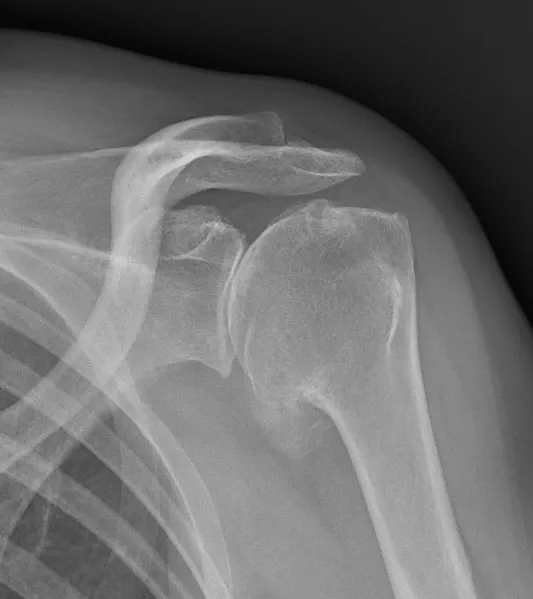

Aspect radiographique d'une omarthrose primitive

Dans un premier temps des radiographies permettent d'avoir une orientation diagnostic en corrélation avec l'examen clinique du chirurgien. Il s’agit du bilan de débrouillage qui sera complété le plus souvent par un arthro-scanner (plus rarement une IRM).

- L'arthrose primitive qui est liée à l'usure du cartilage sans étiologie particulière. Il existe des formes familiales mais le plus souvent c'est une dégénérescence liée à l'âge. La dégénérescence entraîne le frottement des os les uns contre les autres. Cela conduit à la formation d'éléments osseux appelés ostéophytes qui limitent progressivement les amplitudes articulaires (raideur). L'inflammation de l'articulation évolue par poussées qui entrainent des douleurs.

- L'arthrose secondaire est une usure du cartilage qui survient secondairement:

- au mauvais fonctionnement ou à la rupture des tendons de la coiffe des rotateurs. On parle alors d'omathrose excentrée. Dans ce cas la prothèse qui sera mise en place sera une prothèse inversée qui remplacera également la fonction des tendons de la coiffe des rotateurs.